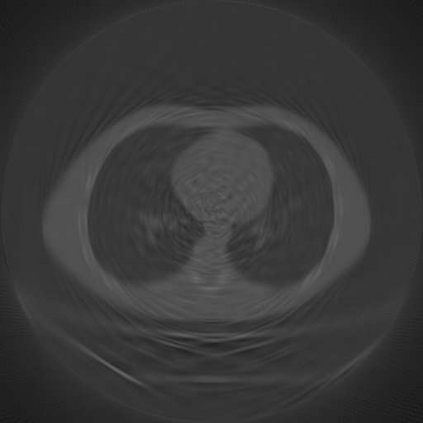

Sparse-view computed tomography (CT) is known as a widely used approach to reduce radiation dose while accelerating imaging through lowered projection views and correlated calculations. However, its severe imaging noise and streaking artifacts turn out to be a major issue in the low dose protocol. In this paper, we propose a dual-domain deep learning-based method that breaks through the limitations of currently prevailing algorithms that merely process single image slices. Since the scanned object usually contains a high degree of spatial continuity, the obtained consecutive imaging slices embody rich information that is largely unexplored. Therefore, we establish a cascade model named LS-AAE which aims to tackle the above problem. In addition, in order to adapt to the social trend of lightweight medical care, our model adopts the inverted residual with linear bottleneck in the module design to make it mobile and lightweight (reduce model parameters to one-eighth of its original) without sacrificing its performance. In our experiments, sparse sampling is conducted at intervals of 4{\deg}, 8{\deg} and 16{\deg}, which appears to be a challenging sparsity that few scholars have attempted before. Nevertheless, our method still exhibits its robustness and achieves the state-of-the-art performance by reaching the PSNR of 40.305 and the SSIM of 0.948, while ensuring high model mobility. Particularly, it still exceeds other current methods when the sampling rate is one-fourth of them, thereby demonstrating its remarkable superiority.